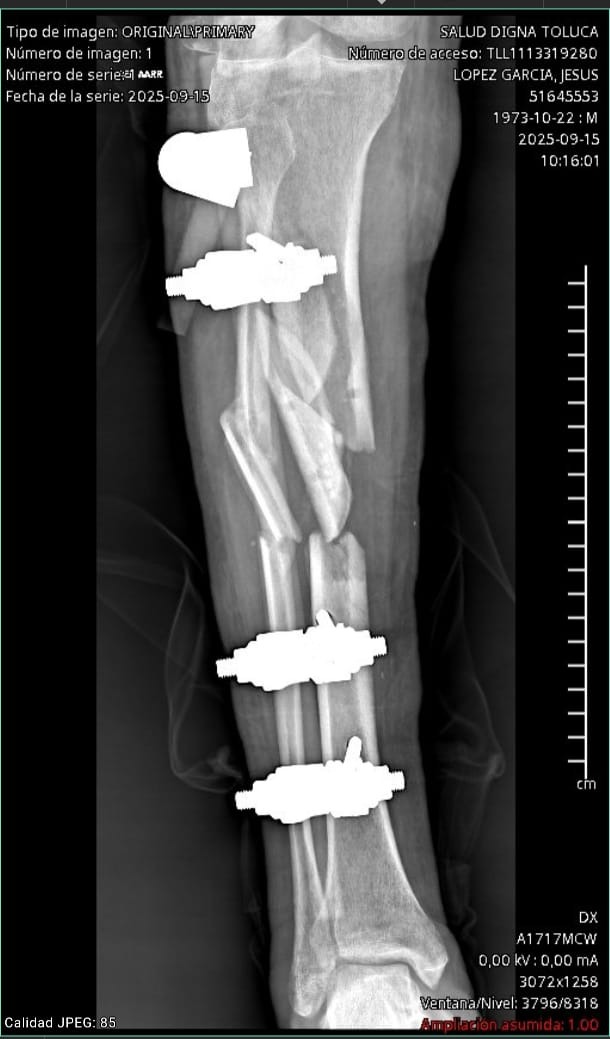

Hace unos meses, en un viaje a Morelia, sufrió un grave accidente en motocicleta. Al salir de una curva perdió el control y chocó contra la barra de contención. El impacto fue tan fuerte que gran parte del hueso de su pierna quedó en el lugar del accidente. Desde ese momento, su vida cambió por completo.

Las lesiones fueron muy severas: fractura de tibia, peroné, fémur, rótula, además de daño en tendones y ligamentos. Desde entonces ha estado hospitalizado en Morelia. Los médicos no han podido operarlo aún porque primero fue necesario controlar el riesgo de infección y salvar la extremidad. Hasta ahora le han hecho 7 lavados quirúrgicos y le colocaron perlas de antibiótico, cuyo costo fue de $45,000 pesos.

Hoy, gracias a Dios, las infecciones ya han sido controladas y por fin los médicos consideran posible la cirugía definitiva para reconstruir su pierna. Sin embargo, esta operación requiere de 17 cm de injerto óseo proveniente de un banco de huesos, además de placas, clavos, tornillos e instrumental especializado. Todo este material, junto con el costo hospitalario, asciende a $225,000 pesos, cantidad que nuestra familia no puede cubrir sola.